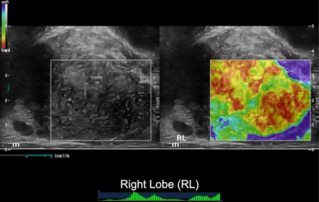

?? ?? ??? ?????(Endocavity volume convex array transducer)(DE10-3WU, Resona 7, ?????)? ??? ??? ???, ??? ?? 1/3 ?? ? ??(anterior vaginal wall)? ???? 18x14 mm ??? ?? ??(an ovoid-shaped formation) with a parietal fine suspension, ????? ??? ???? ??(non-displaced), ????,? CDI ??? ?? ?? ???? ????????. 3D ??? -? ??? ? ??(hyperechoic septa)? ?? ???? ??? ?? ??.

?? ??? ?? ???(Volumetric reconstruction)? ??? ??? ?? ??? ?? ??? ??? ? ??? ?? ??????? ??? ??? ??? ???.